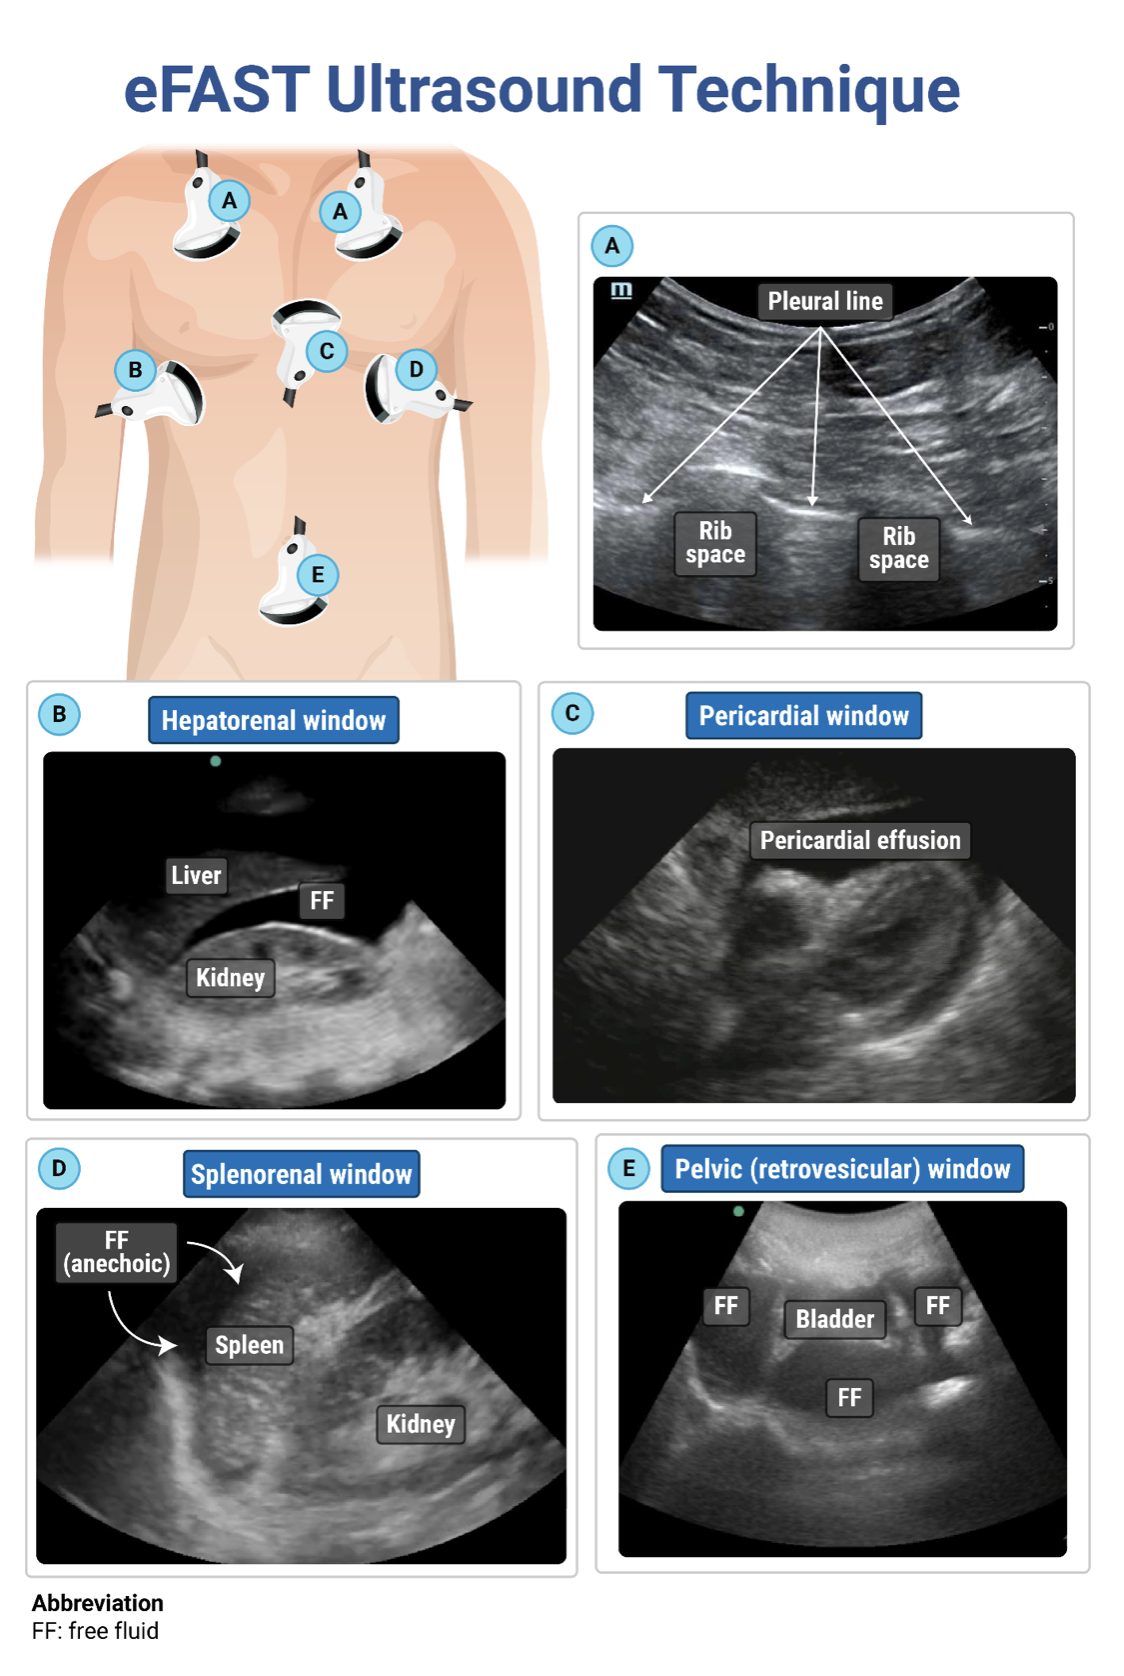

Written and designed to help you understand the core concepts. Questions are just like you'll see on the actual exam, while explanations and illustrations focus on the essential information.

“The most beautiful teaching images on the planet” help you further reinforce the core concepts. Visuals allow you to focus on meaning, group similar ideas, and make better use of your memory (and they're great to look at, too).